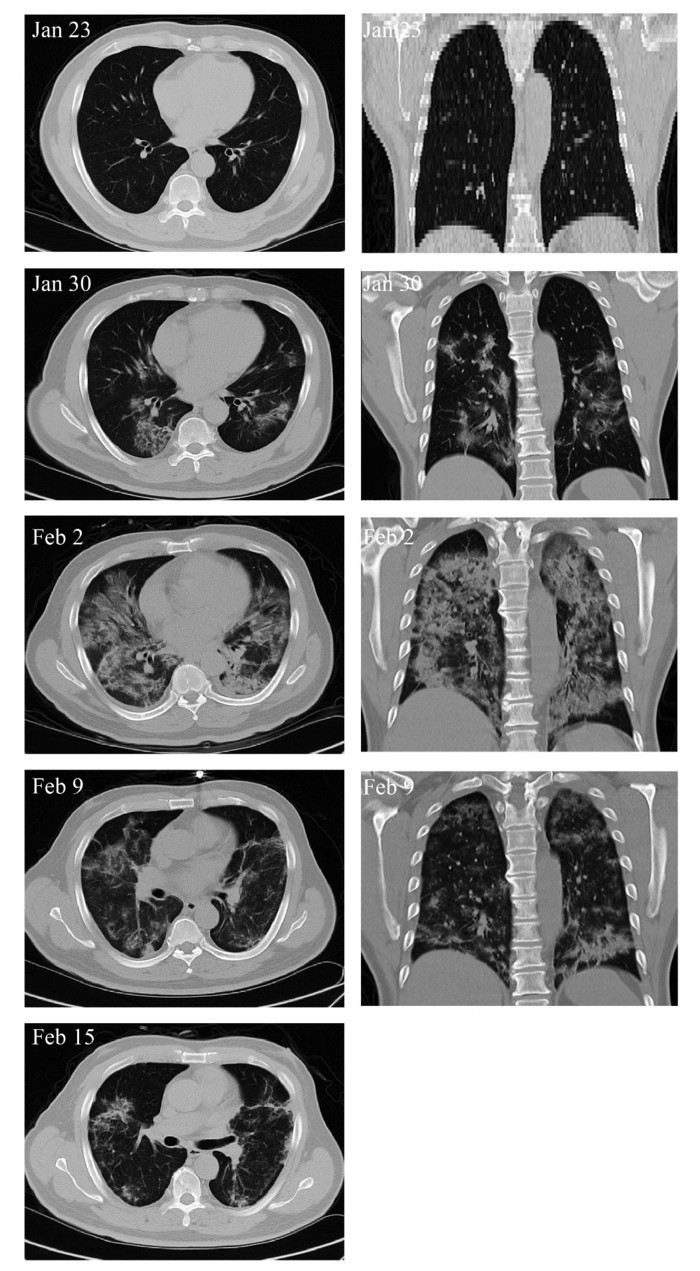

| ▲ 줄기세포 이식 후 폐렴 소견변화 CT 사진. (사진=인하대 제공) |

중국 상하이대학교 로버트 자오 박사가 이끄는 연구팀은 베이징의 유안병원에서 환자 7명을 대상으로 줄기세포 치료를 14일동안진행했다.

연구팀은 치료 전 38.5도 이상 고열과 호흡곤란, 낮은 산소포화도를 보이던 환자들이 줄기세포 치료 시작 2~4일 이후부터 이러한 증상들이 사라지기 시작했으며, 10일 이내에 퇴원을 한 3명을 포함해 모든 환자가 회복됐다는 결과를 발표했다.